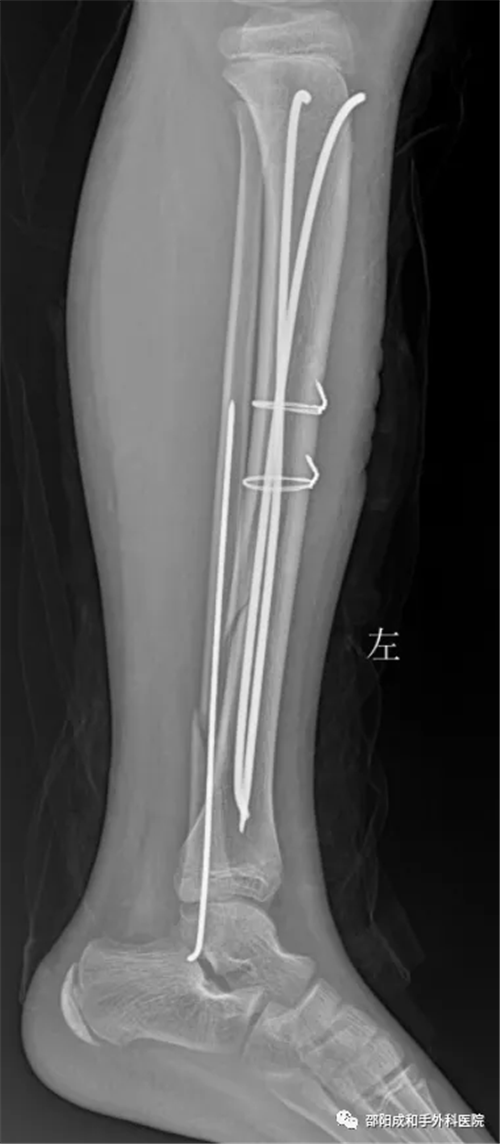

C. 小兒脛腓骨骨折

術(shù)后

術(shù)前圖片